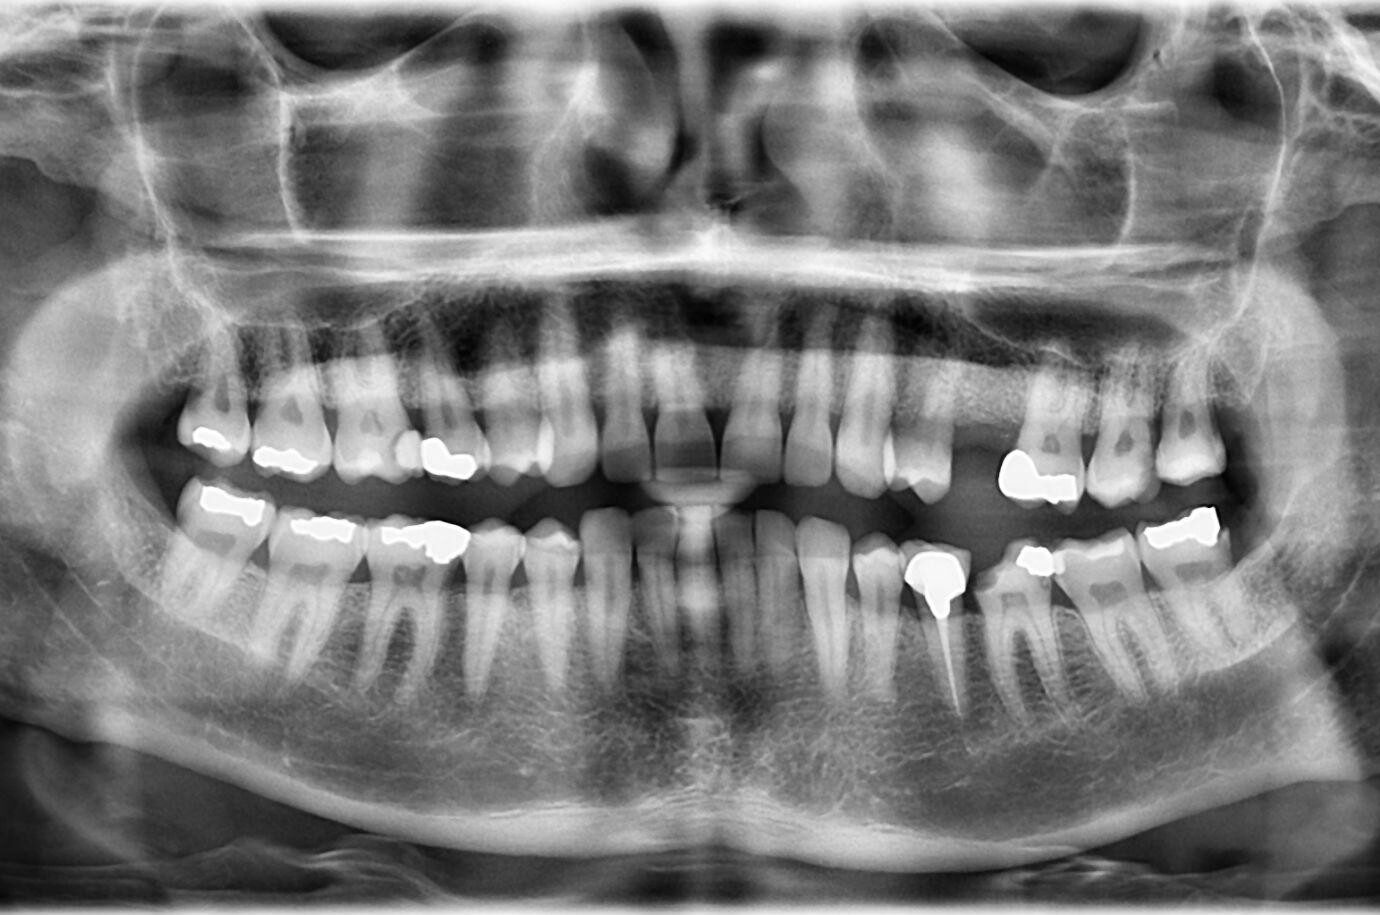

1.  What option cannot be selected for this panoramic X ray?

2 / 23